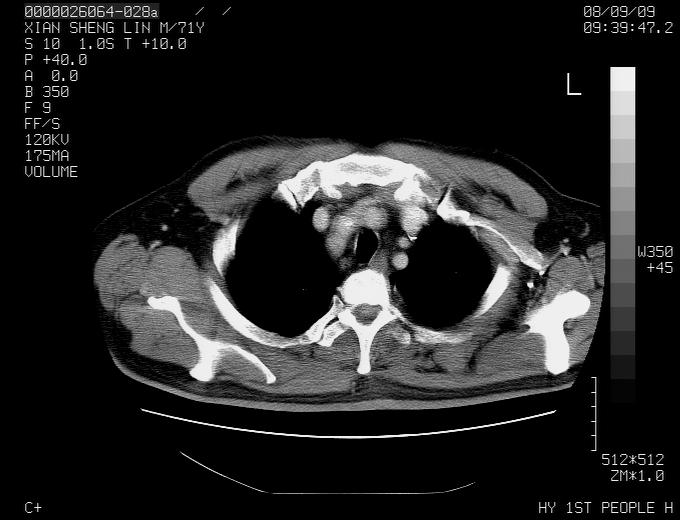

标题: CT15869:男性,71岁,因咳嗽而就诊,请讨论右上肺病变性质 [打印本页]

标题: CT15869:男性,71岁,因咳嗽而就诊,请讨论右上肺病变性质

患者,男性,71岁,因咳嗽而就诊,

典型的右肺中心性肺癌并纵隔淋巴结转移

右肺中心性肺癌并纵隔淋巴结转移可能性大!

病灶中等程度强化 还是支持肺癌诊断

考虑右肺中心性肺癌并右肺门及纵隔淋巴结转移。

1,右肺中心型ca,气管隆突旁淋巴结转移。